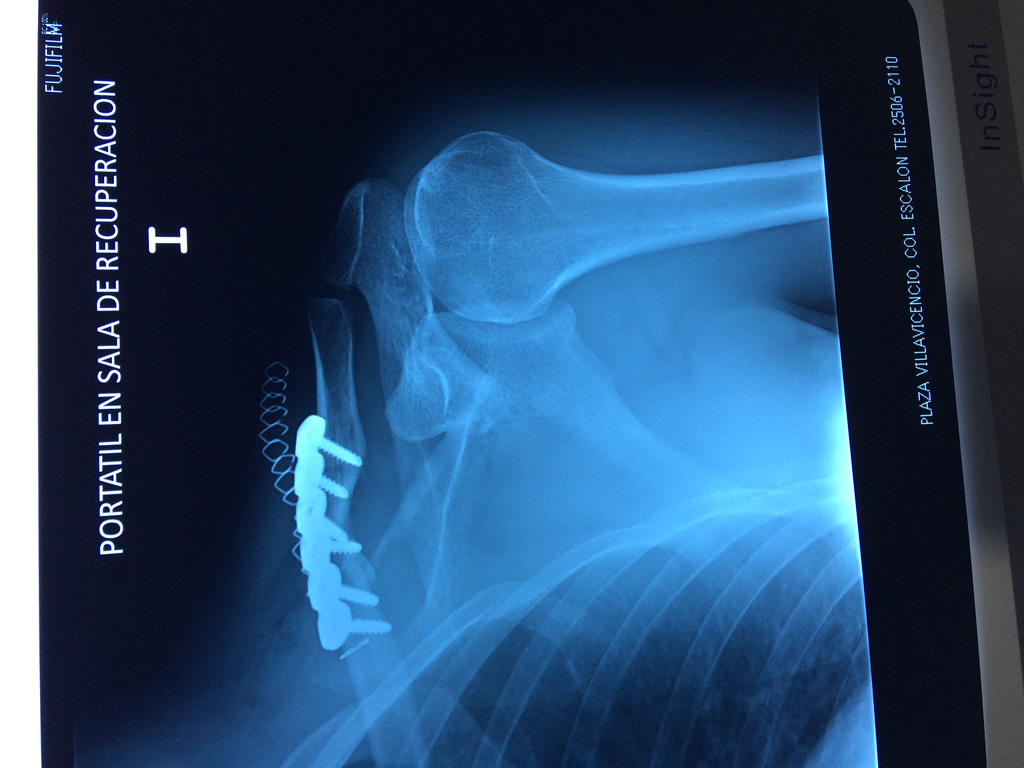

Cirugías

La clavícula es un hueso largo, con forma de "S" itálica, situado en la parte anterosuperior del tórax. Junto con la escápula forman la cintura escapular. Se puede palpar por toda su longitud y se extiende del esternón al acromion de la escápula, siguiendo una dirección oblicua lateral y posterior.